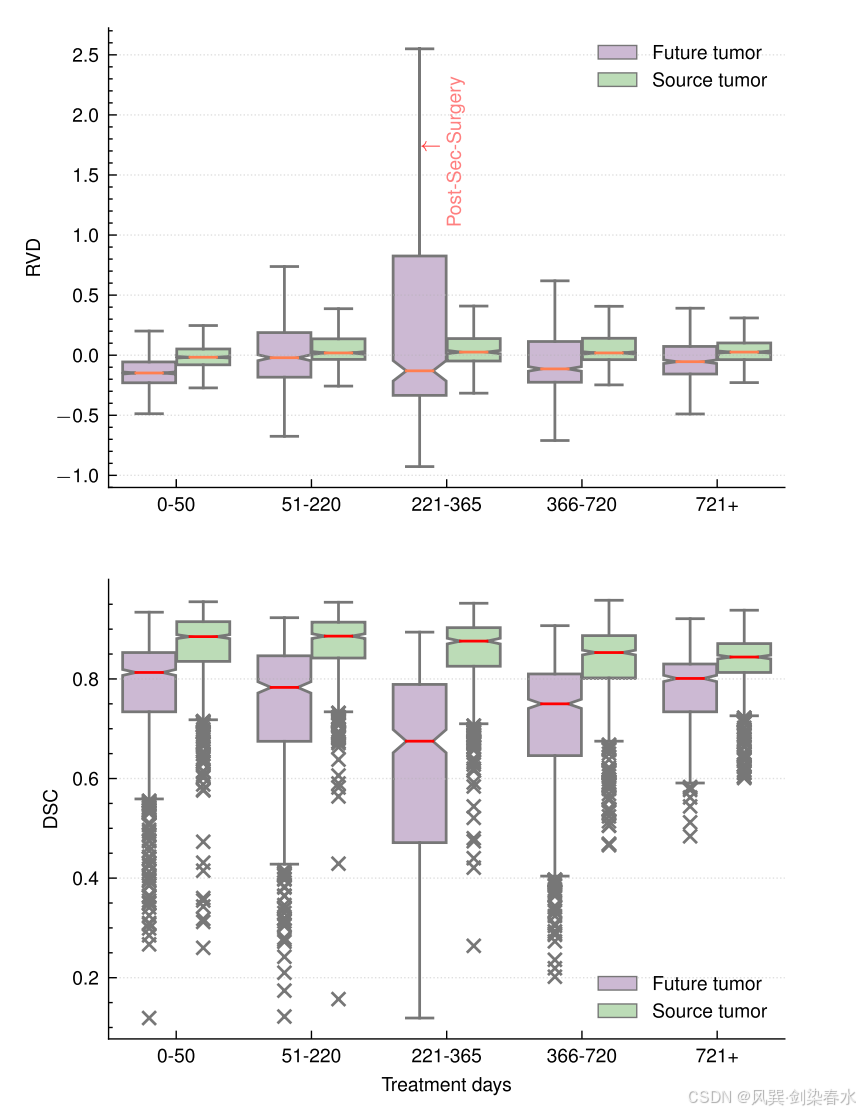

Figure 5 | 治两个箱形图显示了不同治疗日范围内预测的未来肿瘤和源肿瘤的 RVD 和 DSC 分布:请注意,随着 221-365 天范围内的变异性增加,模型性能显著下降,这是因为一例病例(P-1)经历了异常和快速的胶质瘤生长,并在此期间接受了第二次手术治疗;